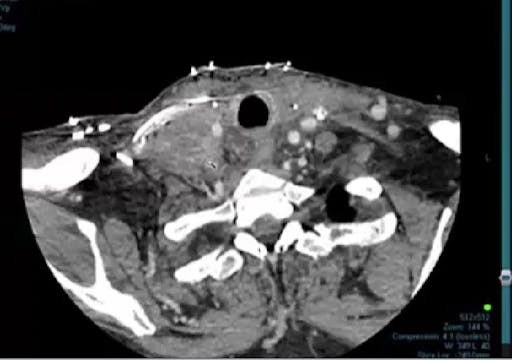

06/30/2025 - Dr. David Sher - Radiation Oncology - Head & Neck

Chartrounds US - Head and Neck Cancer